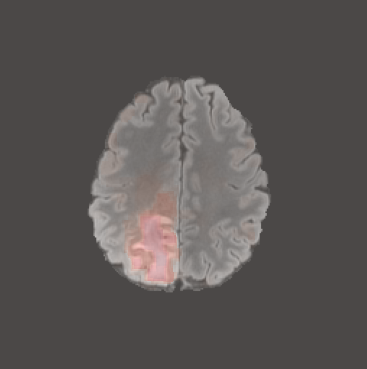

While ACAT revolves around generating counterfactuals, its primary strength lies in accurately identifying pathological regions, which are subsequently employed in a classification pipeline. On the other hand, it falls short in producing credible counterfactual examples, an issue we aim to address in this study. An illustration of this phenomenon is depicted in Figure 2, where we can observe how ACAT is able to generate a saliency map that approximately identifies the pathological region (e, bottom row). However, in the counterfactual example, the lesion remains visible (e, top row). In contrast, our approach not only refines the saliency map but also generates a counterfactual image where the pathology is completely eliminated (f).

4.3 Counterfactual Examples

In Figures 2 and 4 we display examples of healthy images and anomaly maps obtained with the different approaches. We can observe that f-Ano GAN is not able to generate credible counterfactuals and generally produces images of poor quality and unrealistic appearance. On the other hand, the approaches based on diffusion models are able to create more high-quality results. However, the ones obtained with CG and CFG seem to present some artifacts, which may not only impact the realism of the counterfactual examples but also the precision of the anomaly maps obtained from them. In order to better quantify the capability of these methods to accurately segment pathological areas, we compute the Dice scores of the anomaly maps they generate.